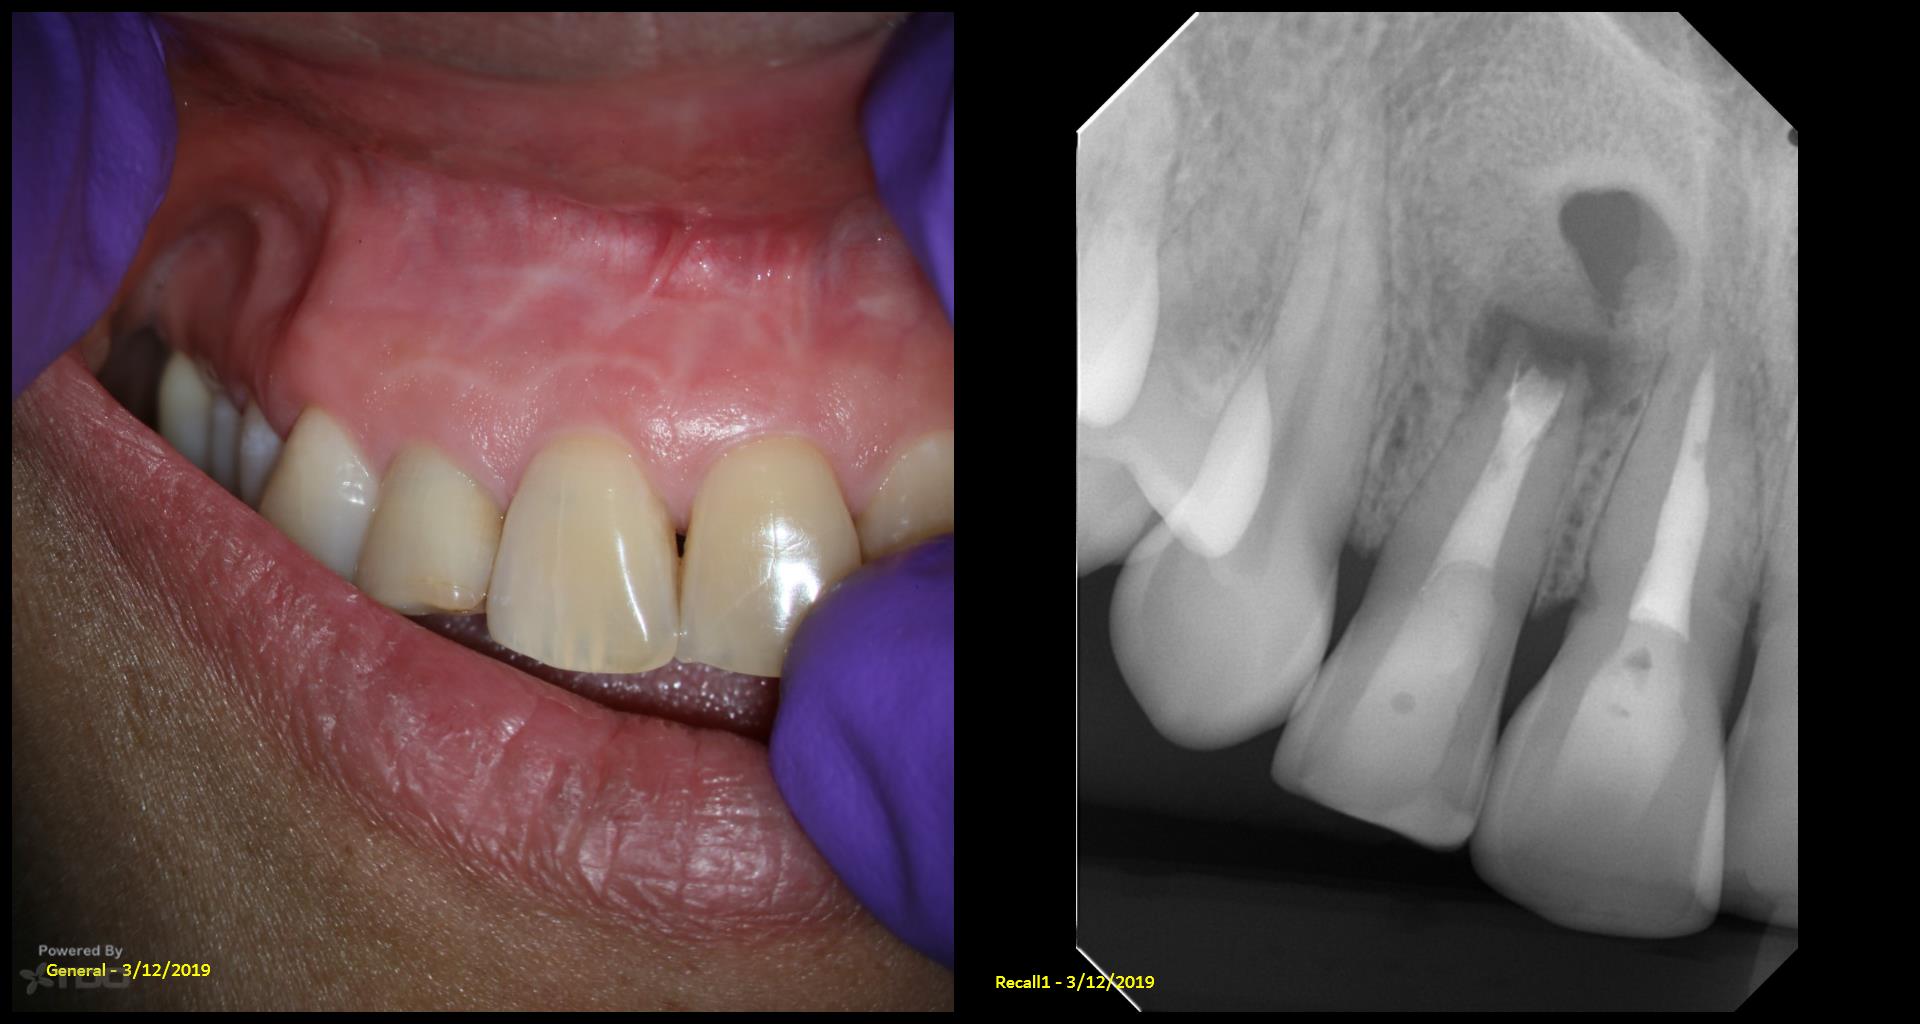

Do you have the previous review x ray s,

Interesting case, Gary. Asymptomatic, but 17-year recalls are crucial! Maybe a bitewing radiograph to check for interproximal caries? A preventative approach avoids future, more involved treatment. Reminds me of needing a winning strategy in Retro Bowl to avoid penalties later on!